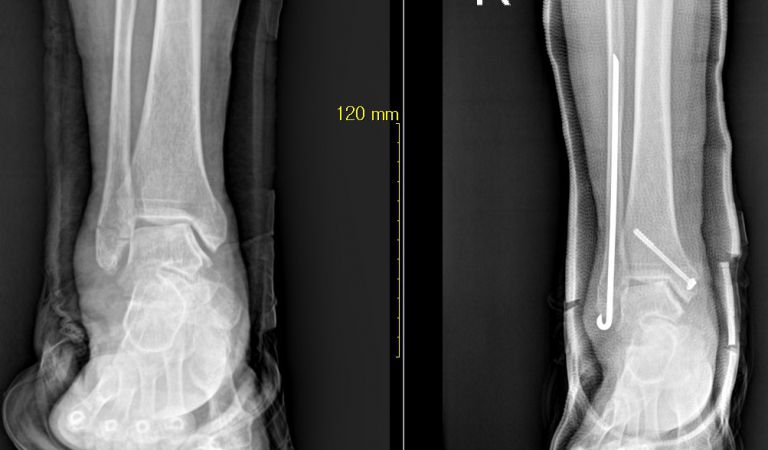

골절 내고정 제거술

수부 골절 불유합수술